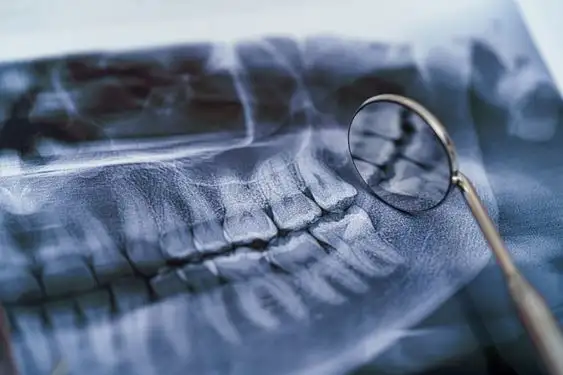

Подробный Обзор: Панорамный снимок зубов в Броварах